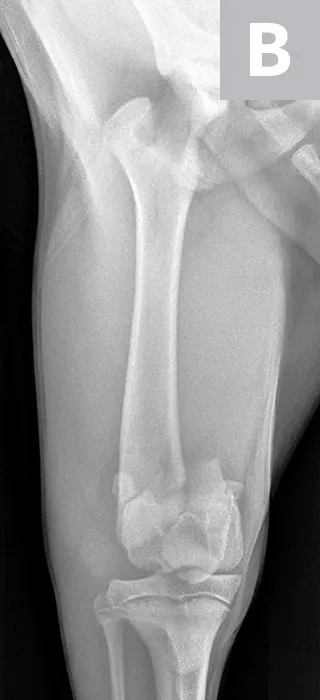

Maggie was managed overnight with analgesia (ie, hydromorphone [0.05 mg/kg IV q4-6h]) and nursing care. The following morning, Maggie was placed under general anesthesia and given a morphine epidural, and surgical fixation of the fracture was performed through a craniolateral approach to the stifle. The distal femoral physis is W-shaped and has inherent stability when reduced; however, additional stabilization is required to provide adequate resistance to the forces applied across the fracture and to allow for the stability needed for healing. Two smooth pins were placed obliquely across the fracture site (Figure 2). The pins should cross proximal to the fracture site to provide maximal repair stability.7

Figure 2

Lateral (A) and craniocaudal (B) radiographs of the femur immediately after open reduction and internal fixation with 2 cross pins. The pins cross proximal to the fracture site, which is important for stability of the repair.